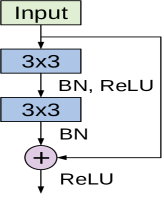

The cornerstone for constructing deep residual networks is the residual module of which two variants are depicted in Figure 3. The left path of the residual module in Figure 3 (a) is composed of two convolutional layers, which apply kernels and preserve the spatial dimensions. Batch normalization and ReLU activation are also applied. The right path is the skip connection where the input is added to the output of the left path. This variant is used in the ResNet18 model. Another variant of the residual module named the bottleneck residual module is depicted in Figure 3 (b), in which the input signal also passes through two branches. However, the left path performs a series of convolutions using and kernel sizes, along with batch normalization and ReLU activation. The right path is the skip connection, which connects the module’s input to an addition operation with the output of the left path. This variant is utilized in ResNet50 and ResNet101 models.

A deep residual network is constructed by stacking multiple residual modules on top of each other along with other conventional convolution and pooling layers. For our experiments we adopt three variants of ResNet, the ResNet18, ResNet50 and ResNet101 models. The full configurations and overall structure about each model are given in [40].